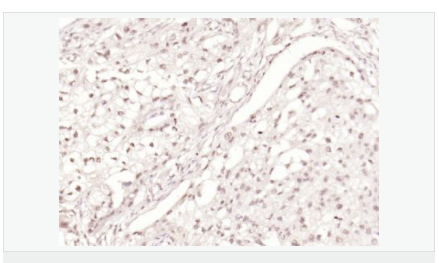

| 產品應用 | WB=1:500-2000 ELISA=1:5000-10000 IHC-P=1:100-500 IHC-F=1:100-500 Flow-Cyt=1μg/Test ICC=1:100 IF=1:100-500 (石蠟切片需做抗原修復) not yet tested in other applications. optimal dilutions/concentrations should be determined by the end user. |